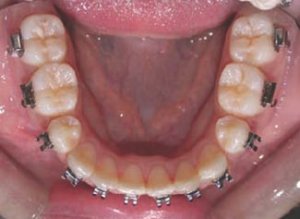

Figure 5--Clinical appearance prior to orthognathic surgery. The mandibular asymmetry and associated maxillary occlusal plane cant are evident. (Please note that photos in occlusion were taken in CR).

The management of post-traumatic malocclusions is difficult, and often requires a coordinated effort on the part of several dental specialists, and occasionally, novel treatment approaches. The increasing popularity and availability of temporary anchorage devices has enabled the resolution of complex clinical situations that would otherwise have involved a compromised approach and a less than ideal … Read more